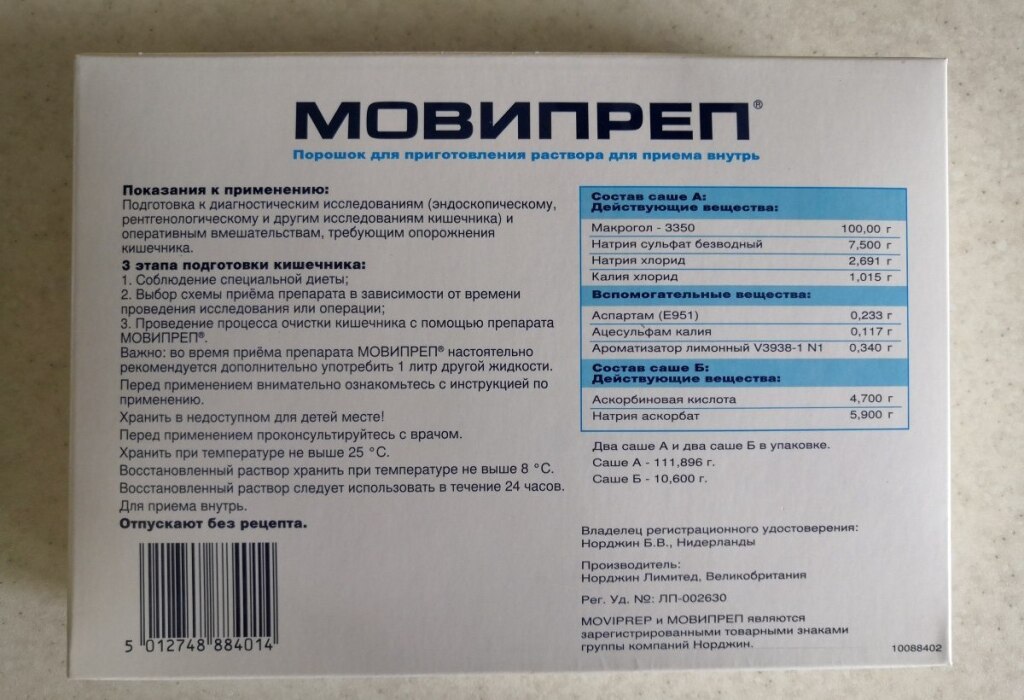

Подготовка к ирригоскопии: необходимые препараты